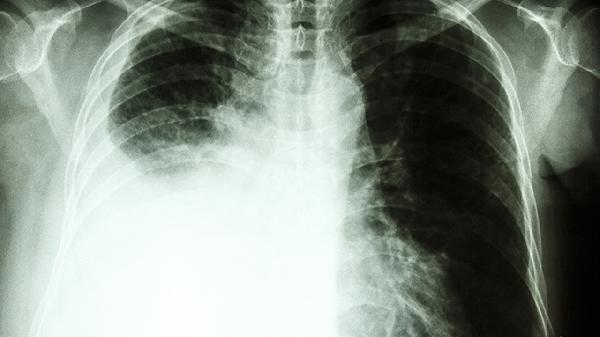

药物中的抗炎成分可抑制前列腺素合成,减轻肿瘤浸润或转移导致的炎性疼痛。对骨转移癌痛、癌性胸腹痛有缓解效果。镇痛效果通常在用药3-5天后显现,重度疼痛需联合其他止痛药物。